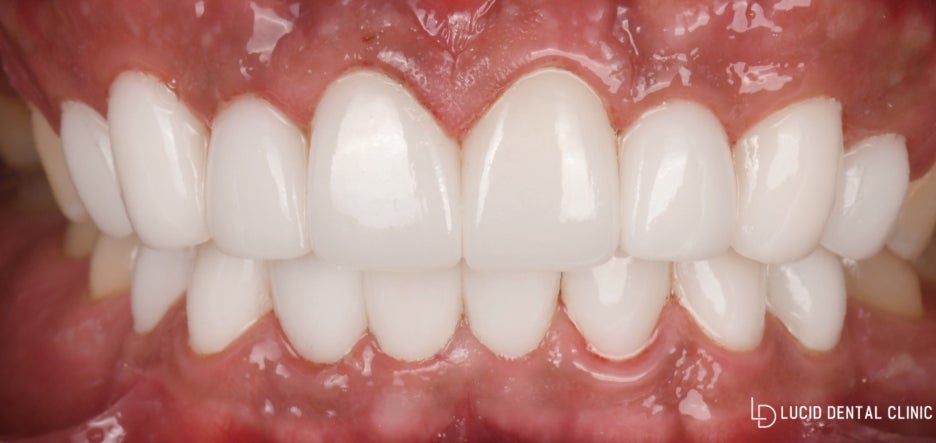

그럼 cerec 밀링머신으로 당일에 나온

루시네이트 결과를 한 번 보도록 할까요?

단 하루 만에 치료를 마친 모습입니다.

처음에 가지고 있던

누랬던 모습은 보이지 않고

가지런하고 밝아진 색조로 더욱 심미성이

높아진 걸 관찰할 수 있게 되었습니다.

- 환자께서는 단 하루 만에 바뀐 모습에

자신도 놀라고 무엇보다 가족이 제일 놀랐다네요.